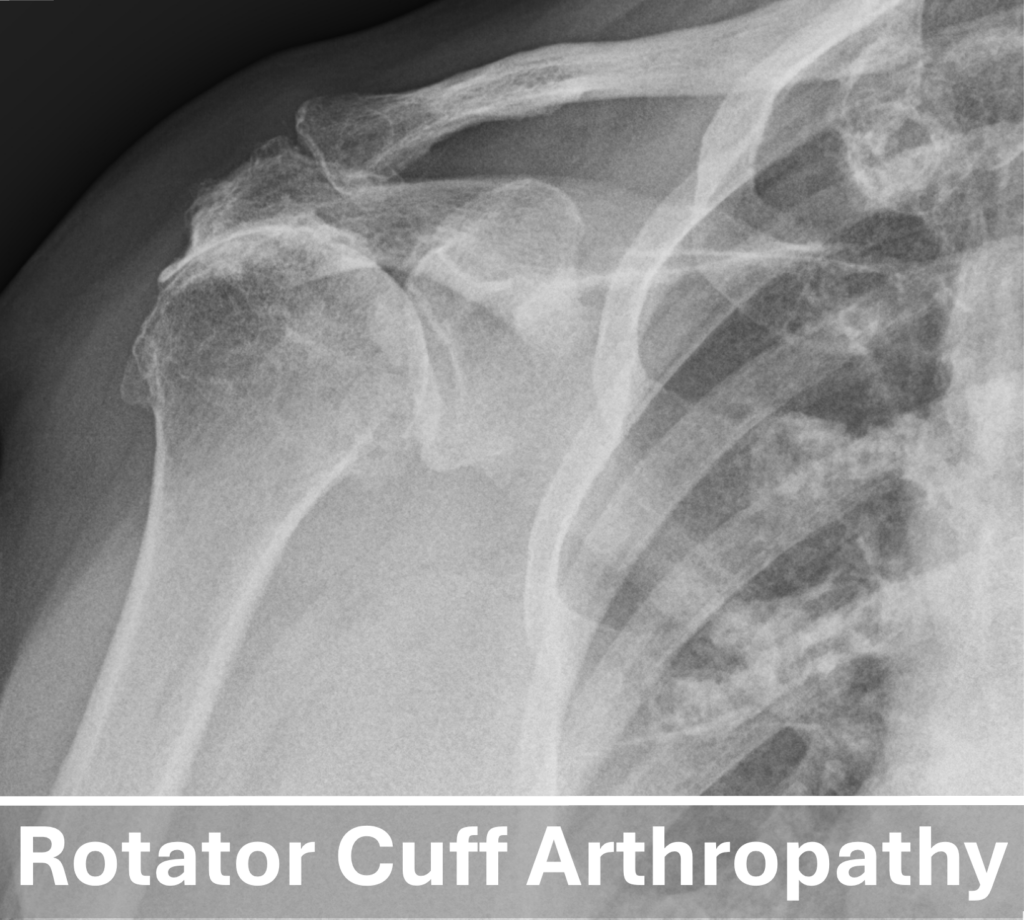

- Rotator Cuff Arthropathy: This is a special kind of arthritis that develops primarily from a chronic loss of a functional rotator cuff.